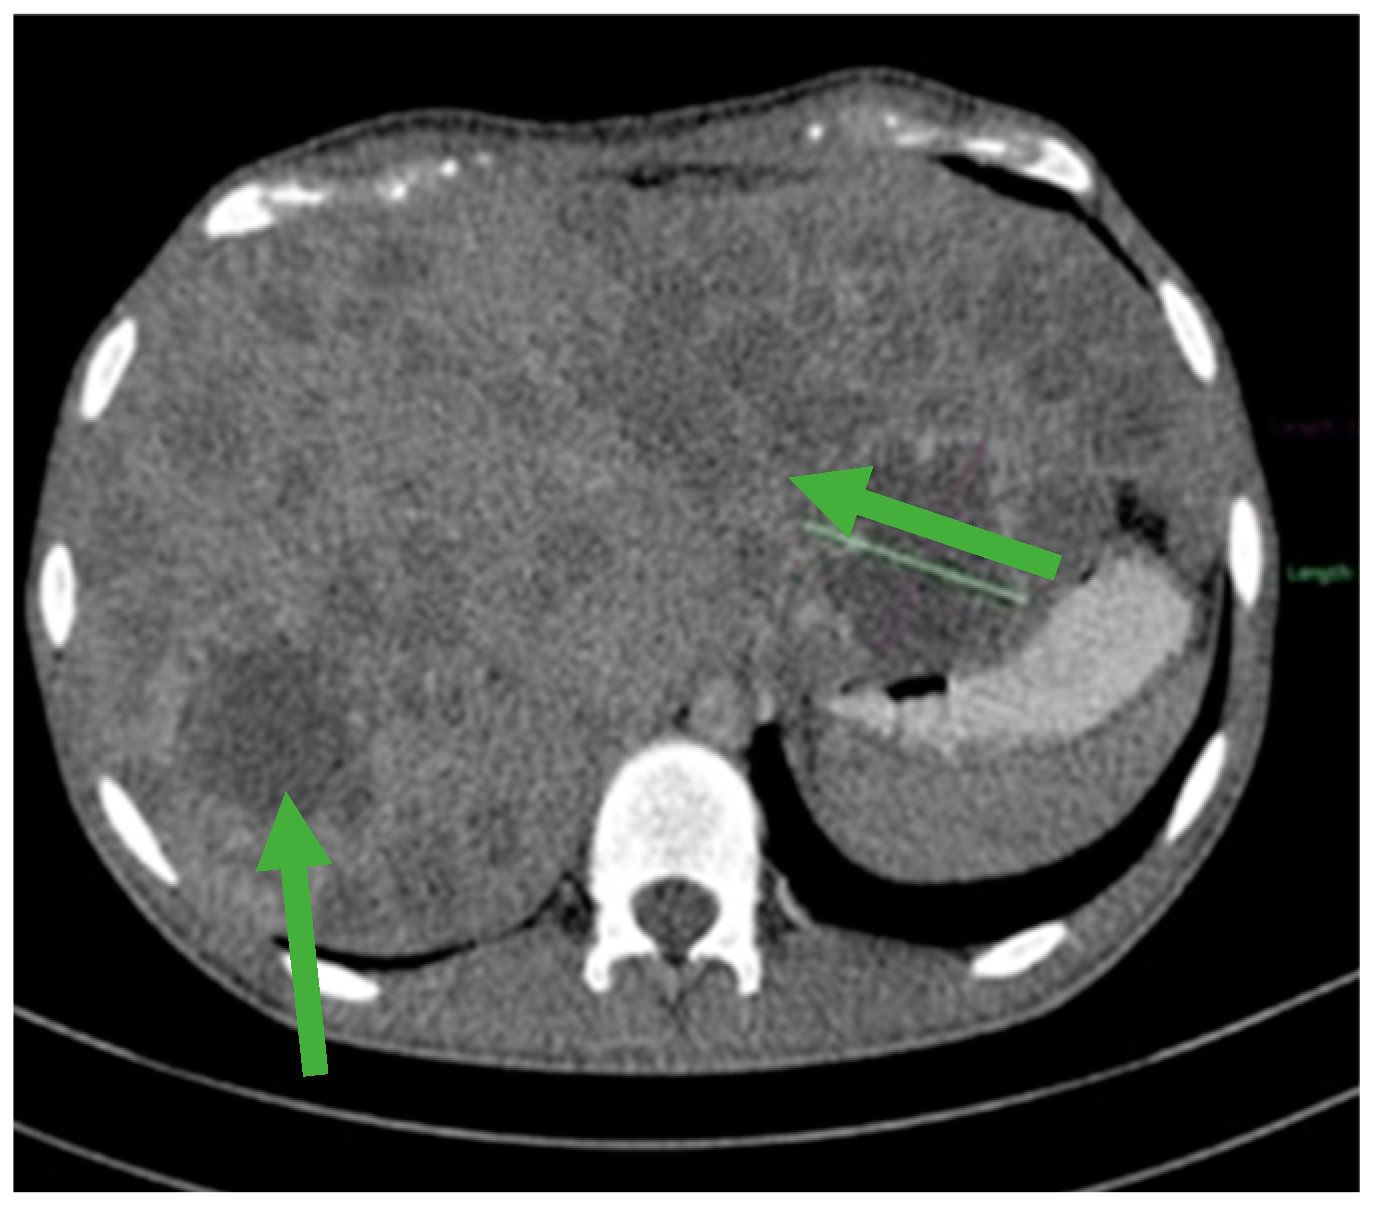

Figure 1.

Contrast-enhanced computed tomography (CT) revealed an irregular, slightly rounded retroperitoneal abdominal mass measuring 70 × 98 × 66 mm (green arrows).

Furthermore, laboratory investigations revealed severe anemia with a hemoglobin level as low as 4.2 g/dL. To gain a comprehensive understanding of the extent of the disease and its impact on the patient’s overall health, an extensive evaluation was conducted. This assessment included Endoscopic Retrograde Cholangiopancreatography (ERCP) and whole-body computed tomography (CT). These diagnostic tests collectively confirmed the presence of an extended retroperitoneal mass (Figure 1), which had invaded the duodenum, thus underscoring the severity and complexity of the patient’s condition.